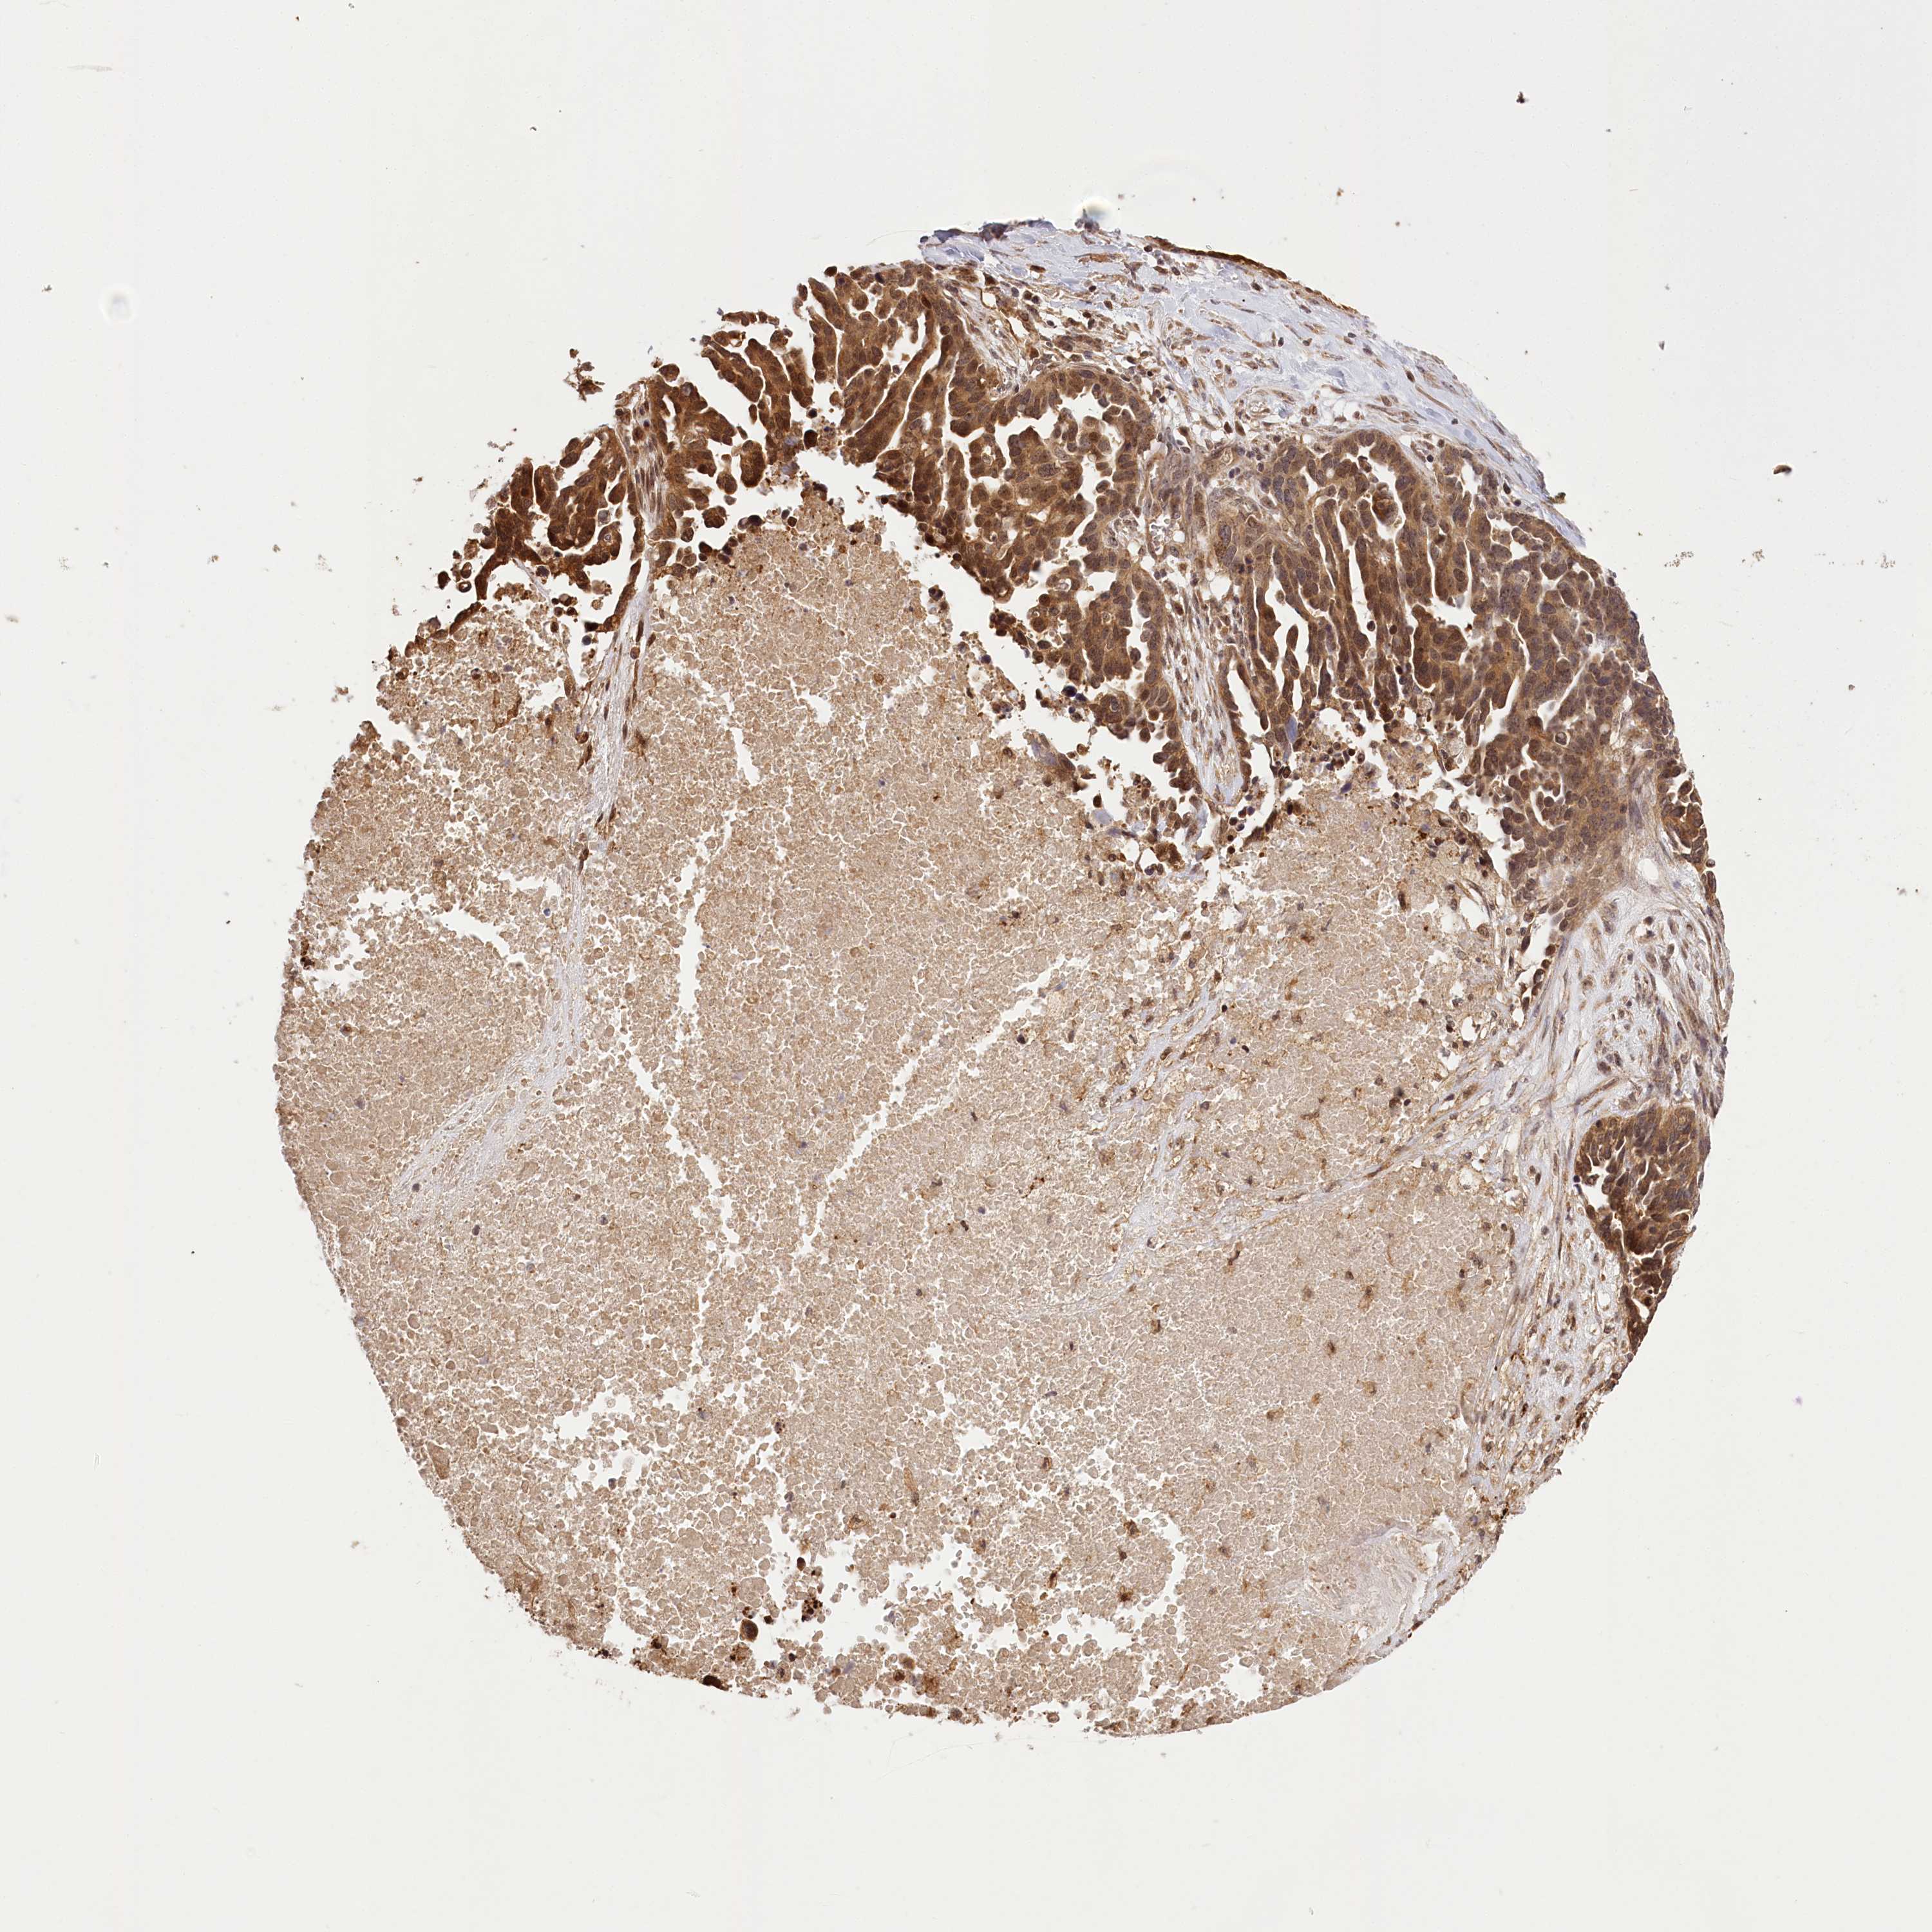

OVARIAN CANCER - Protein expressioni

A mouse-over function shows sample information and annotation data. Click on an image to view it in a full screen mode. Samples can be filtered based on level of antibody staining by selecting one or several of the following categories: high, medium, low and not detected. The assay and annotation is described here.

Note that samples used for immunohistochemistry by the Human Protein Atlas do not correspond to samples in the TCGA dataset.

Antibody stainingi

Antibody staining in the annotated cell types in the current human tissue is reported as not detected, low, medium, or high, based on conventional immunohistochemistry profiling in selected tissues. This score is based on the combination of the staining intensity and fraction of stained cells.

Each image is clickable and will lead to virtual microscopy that enables deeper exploration of all samples and also displays staining intensity scores, fraction scores and subcellular localization as well as patient and tissue information for each sample.

Antibody HPA037811

Antibody HPA037812

Staining

High

Medium

Low

Not detected

Intensity

Strong

Moderate

Weak

Negative

Quantity

>75%

75%-25%

<25%

None

Location

Nuclear

Cytoplasmic/membranous

Cytoplasmic/membranous,nuclear

Cystadenocarcinoma, serous, NOS